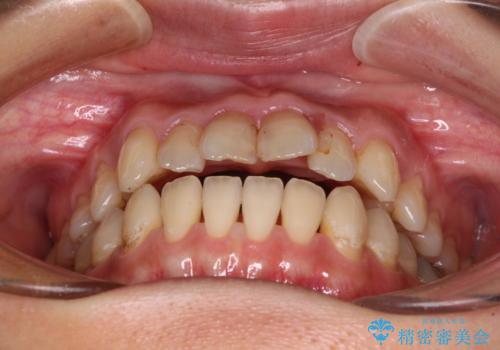

【モニター】開咬を治したい インビザラインによる矯正治療

- 上下前歯の開咬とデコボコを気にして来院された患者様です。

開咬(オープンバイト)はインビザラインによる矯正治療がワイヤー装置と比べて圧倒的に有利であるため、インビザラインによる矯正治療を行うこととしました。

通院されなかった時期があって治療期間が長くなったり、奥歯に抜歯が必要な歯があったりと、治療は一筋縄にはいきませんでしたが、何とか治療を終えることができました。